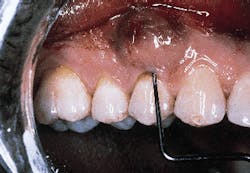

A patient with a periodontal abscess on the buccal of tooth #5 can be seen in photograph #1. Probing reveals a 6 mm pocket.

Photograph #1: An abscess is present on the facial aspect of tooth #5. Probing indicated a 6mm pocket.